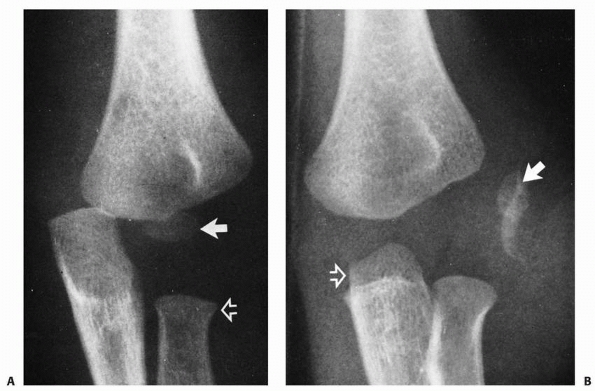

![]() |

FIGURE 15-2 Physeal fractures of the lateral condyle. A. Physeal injury (Milch type II) through the nonossified trochlea. B.

Physeal injury (Milch type I) through the ossific nucleus of the lateral condyle. (Adapted and reprinted with permission from Milch HE. Fractures and fracture-dislocations of the humeral condyles. J Trauma 1964;4:592-607.) |